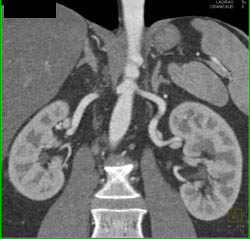

1 Cm Right Renal Cell Carcinoma- See Full Sequence